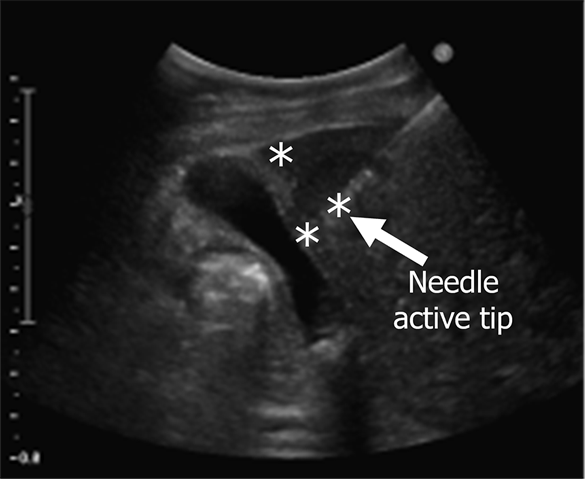

Why improve needle tracking?

Needle’s active tip determines the location of the generated ablation zone, directly impacting the tumour coverage and treatment effectiveness. However, accurate needle identification remains a challenge due to several factors: (1) Due to the in-plane insertion requirement, the needle often veers away from the imaging plane. (2) And the needle often shows poor image quality, especially when inserted at a steep angle or at greater depths. (3) In addition, needle mimics such as the boundary of the gallbladder can resemble the needle, further complicating identification and increasing the risk of misinterpretation. These challenges highlight the need for improved needle tracking methods to enhance accuracy, confidence, and treatment success in ultrasound-guided ablation, as shown in the video below.